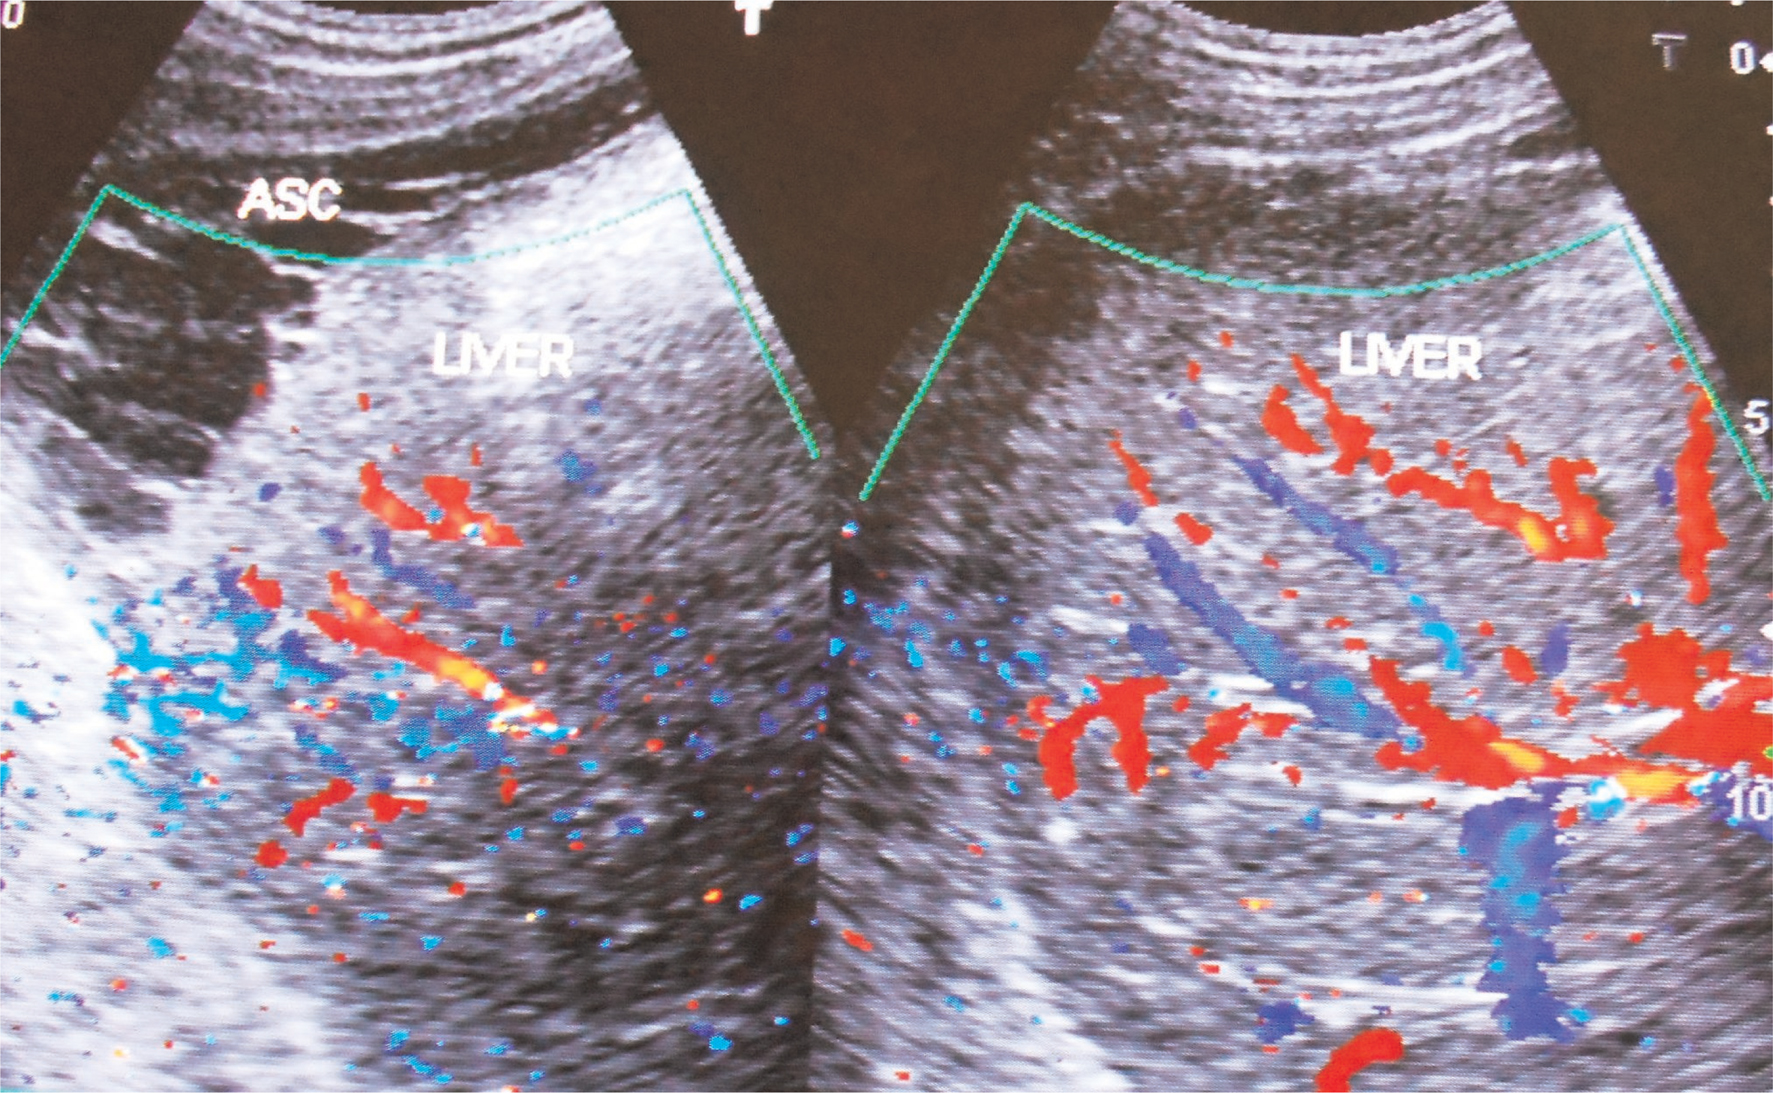

Fig 5

Figure 5. Ultrasonography and color Doppler of a patient with HVCS showing ascites with evidence of chronic peritonitis—Multiple intraperitoneal adhesions. Note the thrombosed, medium-sized branches of portal veins. ASC, ascites. (Copyright: Santosh Man Shrestha).

HVCS develops in any age group of either sex. Ascites in HVCS is common in persons with poor nutrition or history of alcohol abuse, in whom it is usually precipitated by bacterial infection like puerperal sepsis, chronic diarrhea, and fever or by surgery. Even infants on parenteral nutrition develop this condition. Dilated superficial veins in abdomen with upward blood flow are observed (Figure 4). US/CD examination is diagnostic (75). It shows hepatomegaly and ascites often with evidence of bacterial peritonitis, free-floating particles that settle on standing, acute peritonitis and thick peritoneum with adhesions, loculations, or evidence of perihepatitis indicating chronic peritonitis (Figure 5). Segmental stenosis of medium-sized intra-HVs and prominent main HVs with obstruction to blood flow at the HV outlets will be demonstrated in US/CD. IVC at the site of HV outlet shows stenosis with thick posterior wall with recent and old organized thrombi of different ages along its posterior wall (Figure 6). Gallbladder wall is thick and edematous. Neutrophil leukocytosis or left shift and high level of CRP are common at the onset. Bedside inoculations of blood and ascitic fluid in aerobic blood culture bottle during the initial visit are likely to yield positive culture. Hypersplenism is common in patients with HVCS. Such patients presenting with acute ascites may have normal or slightly elevated WBC count but low platelet count. Levels of serum bilirubin, alanine, and aspartate aminotransferase will be elevated. Cavogram and liver biopsy are not necessary for diagnosis. HVCS patient without ascites usually have normal levels of bilirubin, alanine, and aspartate aminotransferase, but US/CD examination shows IVC with localized stenosis with thick echoic posterior wall in at the level of HV outlet and old organized thrombi along the posterior wall of the distal dilated segment.